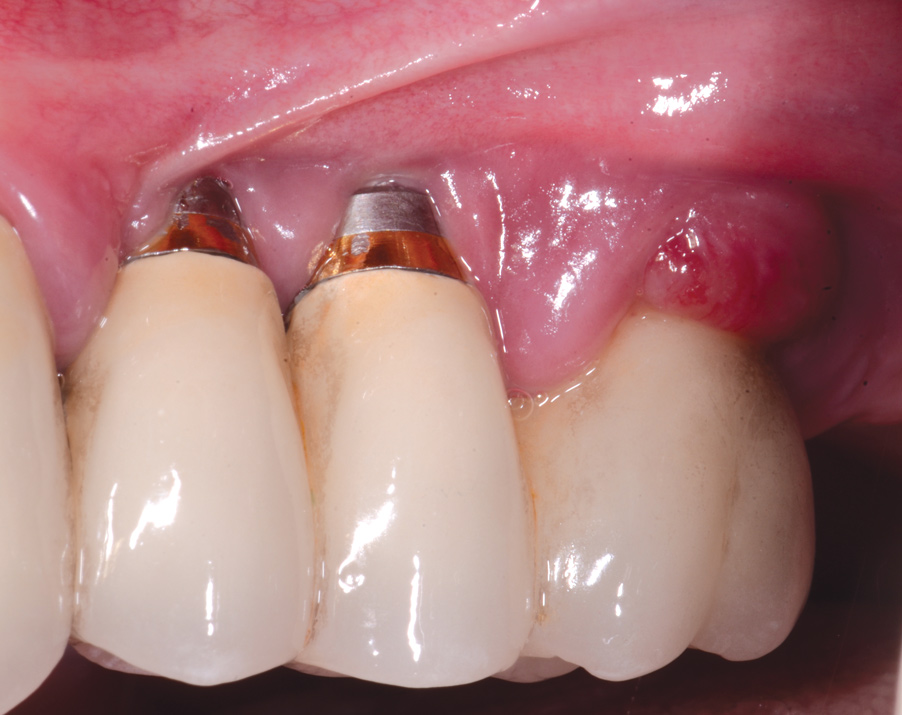

Fig 8. A mucogingival deformity existed on the premolar implants.

Figure 8

Fig 9. A full-thickness flap was elevated and the surfaces decontaminated with air-powder abrasion with glycine-based powder and citric acid.

Figure 9

Fig 10. An autologous subepithelial connective tissue graft was secured in the area with 6-0 chromic gut suture using an interrupted technique. Recombinant platelet-derived growth factor was applied to both the implant surfaces and the graft.

Figure 10

Fig 12. Three years following treatment, stability was achieved with the soft tissue.

Figure 12